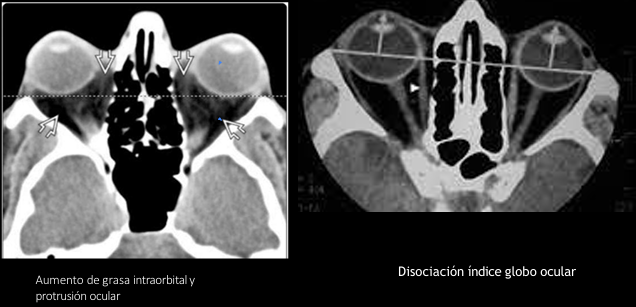

TC en exoftalmos

A

Protrusión ocular anormal

Disociación índice globo ocular - línea intercantal